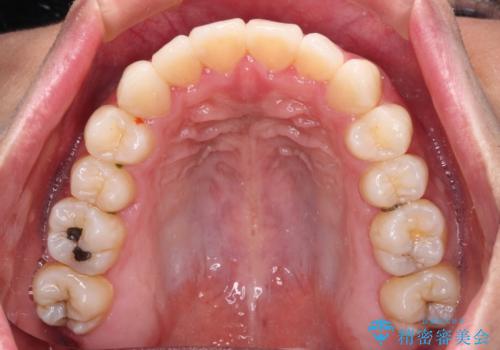

- 全体的なデコボコと、前歯の前に出ている感じを気にして来院された患者様です。

患者様と相談の上、非抜歯にてインビザラインを用いて矯正治療を行うこととし、IPR(歯と歯の間)並びに歯列全体の後方移動により口元の突出感の改善することとしました。